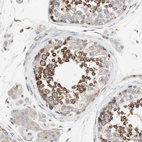

Immunohistochemical staining of human Prostate shows strong cytoplasmic positivity in glandular cells.